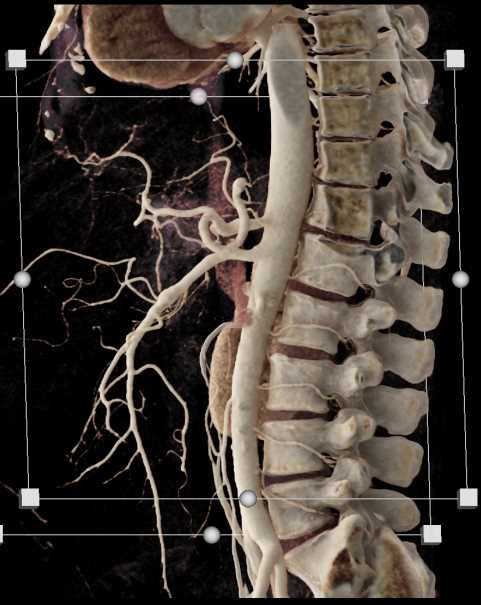

SMA Stenosis